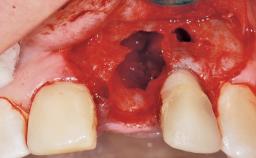

A 42-year-old female patient was referred to our clinic at the School of Dentistry of the University of São Paulo in November 2004, presenting a deficient restoration in the upper left central incisor. The clinical examination revealed no gingival retraction or any signs of gingival inflammation and, therefore, previous periodontal treatment was not considered. The patient presented a high lip line at full smile and a thin tissue biotype. This combination characterized a high-risk situation from an anatomic point of view, which required careful preoperative planning and cautious surgical execution.

Soft Tissue Anatomy Intact Defective

Bone Volume Horizontally and vertically sufficient Horizontally deficient Deficient vertically or deficient vertically AND horizontally

Placement Protocol Immediate implant placement

Socket Integrity Sufficient, with intact bone walls

Bone Volume Sufficient, with intact walls